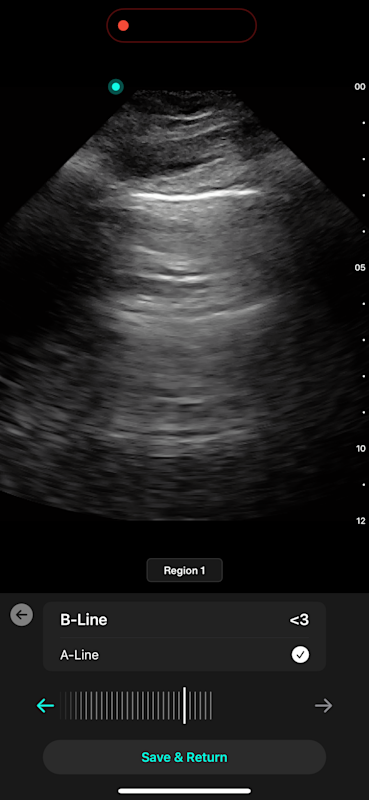

With Lung AI, you can determine the presence or absence of B-lines reliably in seconds.

Lung AI

High Reliability

Excellent agreement with B-lines done by experts (experienced echosonographers) with an Inter Class Correlation (ICC) score of 0.93

High Accuracy

AI matches or exceeds accuracy seen in expert measurements for the presence/absence of A-lines with the Cohen's Kappa Coefficient score of 0.84

High Sensitivity

Lung ultrasound has high sensitivity (94%) and specificity (92%) for counting B-lines to detect Acute Cardiogenic Pulmonary Edema (ACPE) ⁹